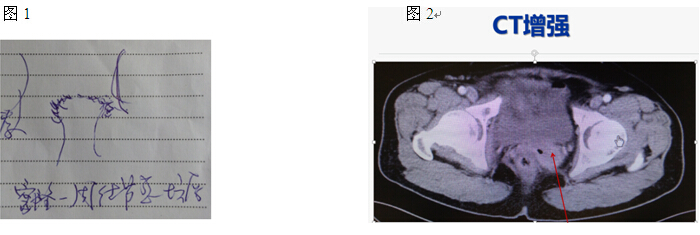

患者55岁女性,G4P2,手术绝经1+年。主因“全子宫切除术后1+年,少量阴道出血2+月”2015-4就诊北京协和医院妇科门诊。患者2014-3因“CIN 2,子宫肌瘤,子宫腺肌症”外院开腹全子宫切除术,术后病理:子宫平滑肌瘤,子宫内膜息肉,CIN 1级,腹水未见瘤细胞。我院病理会诊(14-3外院全子宫切除术后标本)子宫平滑肌瘤,增殖期子宫内膜,慢性宫颈及宫颈内膜炎。术后1年(2015-2)间断少量阴道出血;外院查TCT(-),HPV16(+);2015-4查超声:阴道残端3.8*3.2cm低回声,血流较丰富;右附件2.8*1.8cm无回声。妇科查体(见图1):阴道残端不平,左侧角部可见0.5cm菜花样糟脆肿物,触血(+),残端顶部触及4*3cm质硬不规则结节,无明显压痛,包块质地硬,似与盆壁相连。阴道残端组织活检病理:(阴道残端3点)鳞状上皮黏膜重度不典型增生/原位癌,部分区域可见间质浸润(中分化)鳞状细胞癌,浸润灶散在分布,部分破碎不整(浸润灶可测最大径3mm);(阴道残端6、9、11点)鳞状上皮重度不典型增生/原位癌(VAIN III)。5-18盆腹腔增强CT(见图2):肾脏、输尿管、膀胱(-),直肠壁不厚;阴道残端左侧见软组织密度影,最大横截面积3.14*4.27cm,与前方膀胱分界不清,增强可见明显强化,包块内可见点状气体影;腹膜后、盆腔及双侧腹股沟多发小淋巴结影。既往2年前诊断糖尿病,口服二甲双胍 1片bid,血糖控制良好。生于河北,否认流行病疫区疫水接触史。14岁初潮,5-7天/30天,月经量多,痛经(+),1+年前手术绝经;已婚丧偶,G4P2;爱人13年前因“心梗”去世;性伴侣2位,近1+年否认有性生活。家族史:(-)

回顾该病例,55岁女性,因“CIN2、子宫肌瘤”行TAH术后1年,HPV16+;查体阴道残端不平,左侧角部可见0.5cm菜花样糟脆肿物,阴道残端顶部触及4*3cm质硬不规则结节,似与盆壁相连;超声:阴道残端3.8*3.2cm低回声,血流较丰富;增强CT:肾脏、输尿管、膀胱(-),直肠壁不厚;阴道残端左侧见软组织密度影,最大横截面积3.14*4.27cm,与前方膀胱分界不清,增强可见明显强化,内可见点状气体影;腹膜后、盆腔及双侧腹股沟多发小淋巴结影;阴道残端活检,(阴道残端3点)鳞状上皮黏膜重度不典型增生/原位癌,部分区域可见间质浸润(中分化)鳞状细胞癌,浸润灶散在分布,部分破碎不整(浸润灶可测最大径3mm);诊断“阴道残端中分化鳞状细胞癌II期”,所以下一步治疗应首选放疗。放疗期间定期随访。